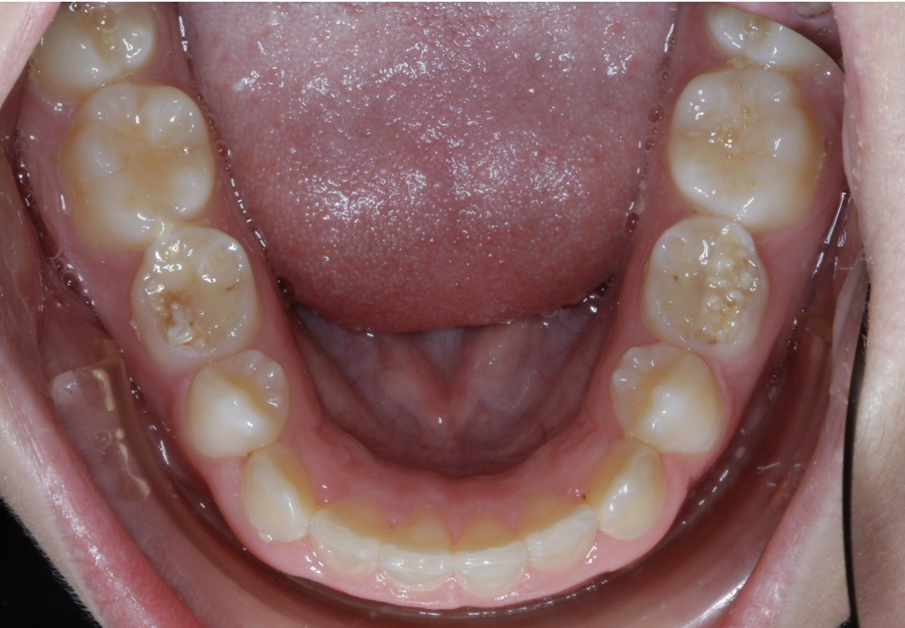

Example 1: Missing teeth

For cases with missing teeth, TADs are placed anterior to the edentulous area, and used as indirect anchorage by tying with a stainless-steel ligature distal to the adjacent tooth (Figs. 30 & 31). A NiTi closing spring is then used to close the space. This is a simple and effective way to maintain anchorage and close space for missing teeth. Especially in cases with congenitally missing premolars, where the primary molar is not a long-term viable option, TADs are a great option in young patients to use as anchorage and close spaces by protraction.

Fig. 30

Fig. 31

Fig. 32

Fig. 33

Fig. 34

Fig. 35

Example 2: Missing premolars

The patient’s teeth are bonded initially, but the retained primary tooth is not bonded. Archwire progression is completed, and once the stainless-steel wire is placed, the retained primary teeth are extracted and TADs are placed mesial to the edentulous area and indirectly tied in order to use as anchorage. An NiTi closing spring is then used from a post on the archwire around the distal on the wire distal to the tooth just adjacent to the edentulous area. The space is then closed. A wire tie is placed to ensure space closure is maintained without continuous use of elastic chain (Figs. 32–35).